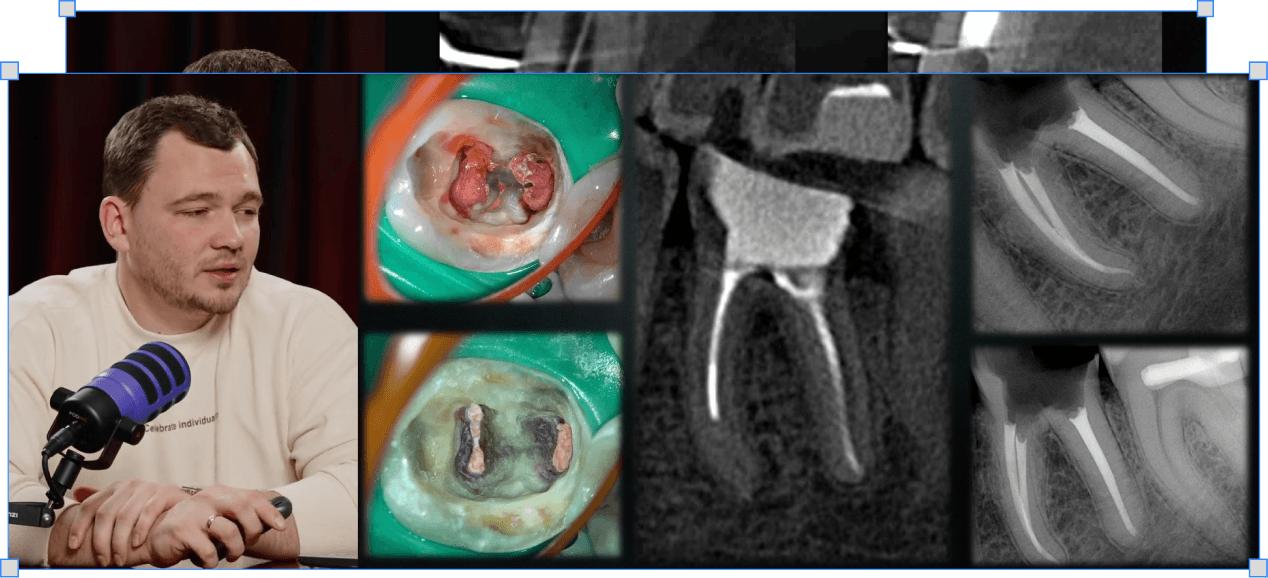

Як розпломбувати штифти, вкладки і гутаперчу – клінічні протоколи

Розпломбування буь-якого типу обтурації і штифтів без ризиків утворення сходинок і перфорацій

Як вилучати анкерні штифти без ризику тріщини кореня

Різниця між латунними і сталевими штифтами, чому механічне викручування — помилка і як це впливає на прогноз зуба

Як орієнтуватись при видаленні скловолоконних штифтів

Робота на сухо — краща візуалізація; орієнтири — волосинки скловолокна і матове коло на дні. Чіткий протокол доступу до каналів

Як вилучати куксові вкладки будь-якої кількості ніжок

Тільки бори по металу; чому багатоніжкова вкладка зводиться до того самого принципу що і анкерний штифт

Як розпломбовувати гутаперчу хлороформом і ротаційними файлами

Хлороформ і ротаційні файли — конкретні оберти для кожного етапу; ксілол для затверділої гутаперчі. Чіткі клінічні протоколи